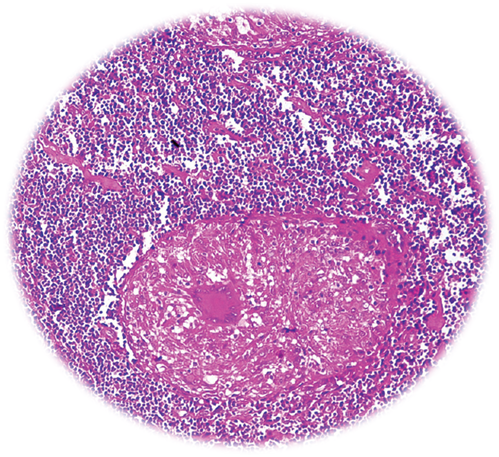

The investigations showed Hb-12.1gm/dl, ESR-45mm 1st hour, total leucocyte count-8700/mm3, differential leukocyte count: neutrophil(63%), lymphocytes(27%), eosinophils(5%), monocytes(4%), and basophils(1%). Biochemical investigations showed Fasting blood glucose-98.0mg/dl, blood urea-30.8mg/dl, serum creatinine-1.1mg/dl, serum bilirubin-0.8mg/dl, AST-34.0 IU/L, ALT-32.3IU/L, Alkaline phosphatase-100.8IU/L. Viral markers for HIV, HBSAg, and HCV was found to be negative. Radiography of Chest showed left sided pleural effusion. Radiography of thoracolumbar spine did not show any abnormality. Fistulo gram delineated the tract which was directed upwards posteromedialy. Fine needle aspiration cytology (FNAC) of right inguinal lymph node showed granular necrotic material with few lymphocytes highly suspicious of tuberculosis. MRI of thoracic spine (T2WI) showed a nodular hyperintense intramedullary lesion at T4 vertebral segment with surrounding hyperintense edema extending from T2to T6 vertebral level (Figure 1). With T1 contrast isointense lesion at D4 vertebral segment showed thick ring enhancement. Colonoscopy also showed a large ulcer in the lower part of rectum suggestive of Tuberculosis (Figure 2). The histology of biopsy material taken from perianal lesion showed caseating necrosis, epithelioid cells with Langhan’s type multinucleated giant cells suggestive of Tuberculosis (Figure 3).

Figure 2 Colonoscopy showing ulcerated lesion present at 3-6cm level over right and posterior walls covering almost half the circumference of the lumen with uneven floor mucosa and multiple punctate ulcers. Surrounding mucosa is rolled out and elevated.

Figure 3 Biopsy showing caseous necrosis, epitheloid granuloma and Langhan’s type multinucleated giant cells.